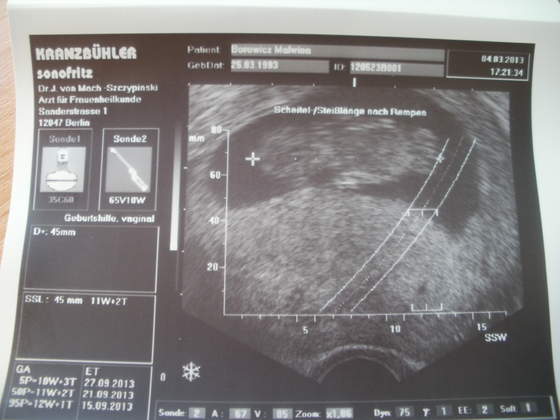

serduszko ładnie mocno biło

A to nasz bąbel :

nic porządnie nie widać